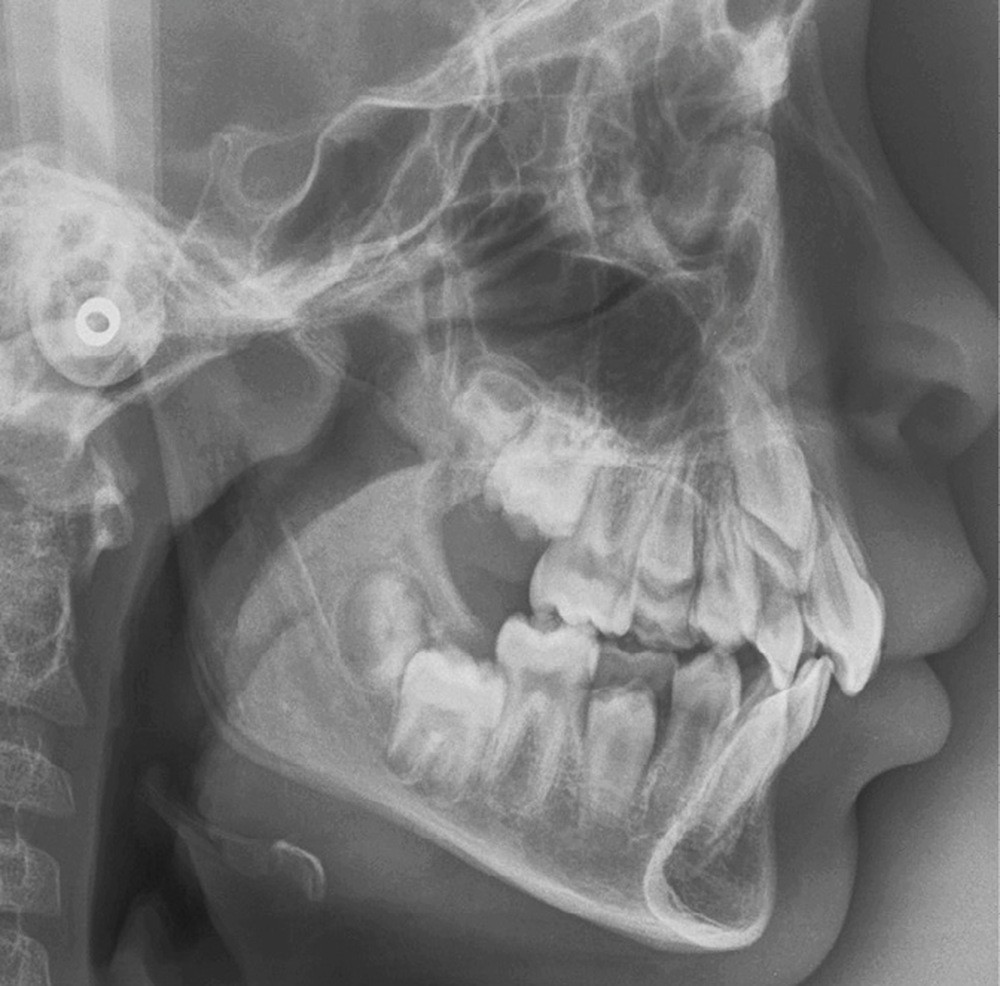

Le profil est convexe et associé à une inocclusion labiale au repos. Il s’agit d’une classe II squelettique sur un schéma facial normodivergent. Les rapports occlusaux sont de classe II bilatérale (complète au niveau molaire) avec des incisives inférieures vestibulo-versées. La 21 est géminée et la 11 vraisemblablement fusionnée avec un germe surnuméraire, sans altération de la formule dentaire. Du fait du diamètre mésiodistal fortement augmenté des incisives centrales, et du manque de place à l’arcade maxillaire qui en découle, les 12 et 22 sont en inversé d’occlusion en palato position. Les 53 et 63 sont persistantes sur l’arcade avec une inclusion en transposition incomplète de la 13, dont la cuspide se situe entre la racine de la 12 et celle de la 11 résorbée (fig. 1d-g).

L’aspect inesthétique des incisives maxillaires (avec une impossibilité de réduction amélaire suffisante du fait des diamètres mésio-distaux radiculaires augmentés) et le pronostic réservé de la 11 (résorption radiculaire marquée) conduisent à la décision d’extraire les deux incisives centrales [1].